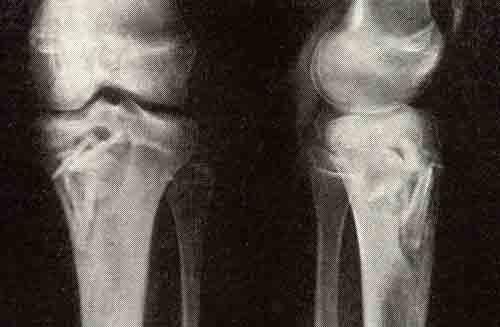

Повышена местная температура. Цвет кожи нормальный. На рентгеновском снимке в проксимальном отделе большеберцовой кости большой очаг разрежения (4X3 см) с гладкими ровными контурами, не содержащий секвестров. Вокруг очага выраженный склероз.

Гистологическое исследование — хронический воспалительный процесс. При посеве получен рост золотистого стафилококка. Осмотрена через 1,5 года. Здорова, жалоб не предъявляет. На рентгеновском снимке явления перестройки гомотрансплантатов.

Изолированный абсцесс большеберцовой кости у девочки 14 лет: до лечения, результат после резекции и гомопластики и результат через 1,5 года.